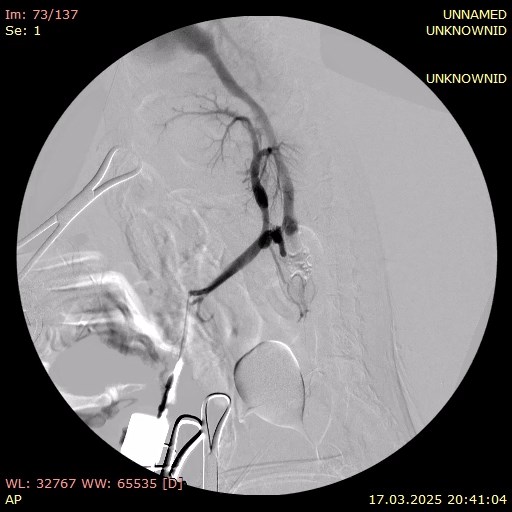

Портография выявила множественные шунты: между портальной веной и каудальной полой веной, а также два спленоазигональных шунта (фото 5).